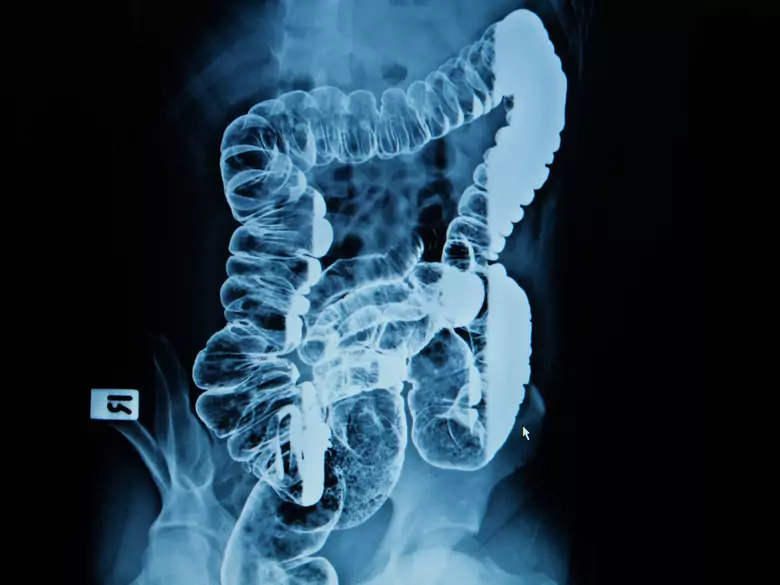

PantherMedia

Badanie jelita